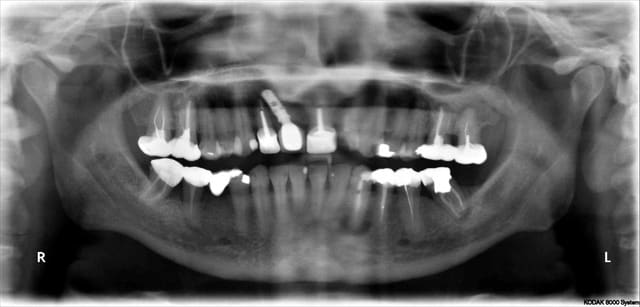

Céramik comme promis Ma réponse en image 2ans après

1 Pano du cas

2 Pano qui a déclenché tous ces gentils commentaires

5 Pano aujourd'hui (le secteur 4 fichu???)

C'est un implant Léone

L'implant Leone semble donner des résultat interessant.

Pour la pano, les trucs noirs sous les apex, ça ne t'inquiètent pas ? Comme sous la 33 ?

En relisant tout le sujet, on lit qu'effectivement, les kystes de 20 ans , stable ne l'inquiete pas.